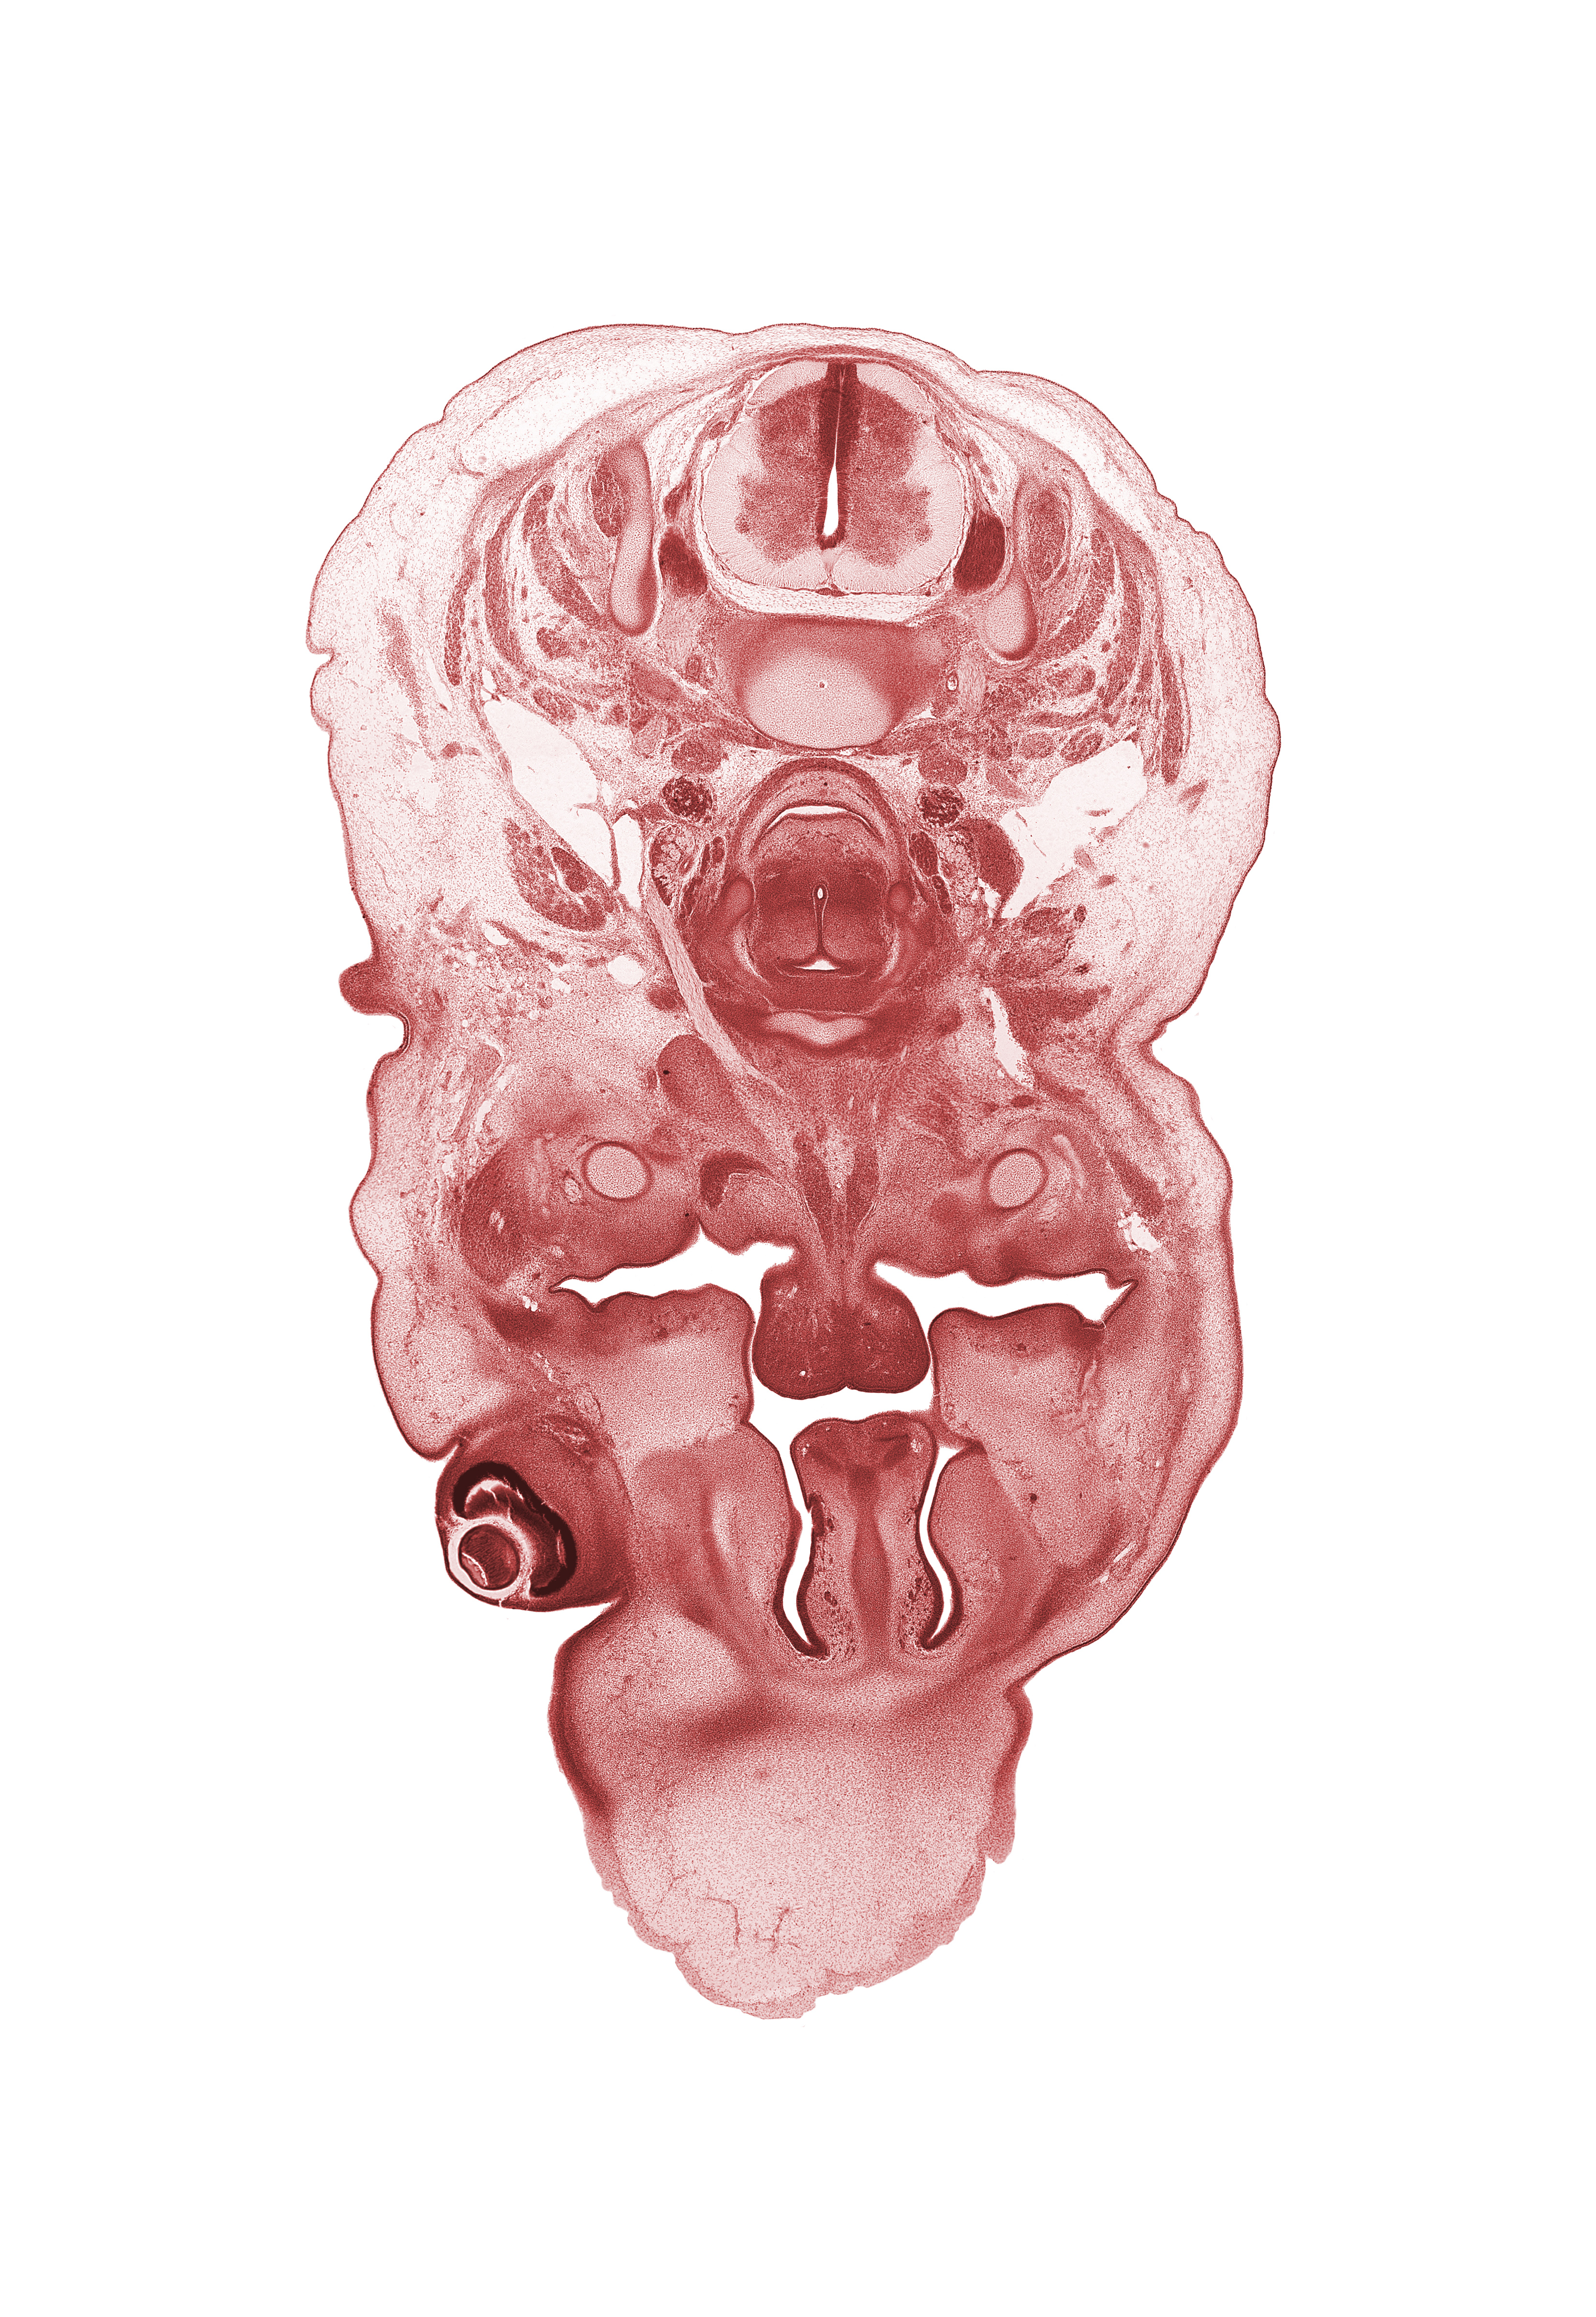

Carnegie Embryo #462 | Location: 5-04-03

Keywords: C-5 spinal ganglion, body of hyoid (pharyngeal arch 3 cartilage), body of tongue, cornea, dorsal horn of grey matter, frontal prominence, geniohyoid muscle, hypoglossal nerve (CN XII), inferior ganglion of vagus nerve (CN X), internal carotid artery, internal jugular vein, jugular lymph sac, middle cervical sympathetic ganglion, nasal capsule, nasal cavity (nasal sac), nasal septal cartilage, palatine shelf, pharyngeal arch 1 cartilage (Meckel), platysma muscle, ventral horn of grey matter, vertebral artery

Source: The Virtual Human Embryo.